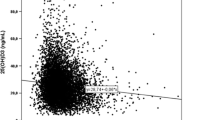

The CIE-weighted UV radiation increased from 0.36 Wh/m2 in December to 24.25 Wh/m2 in July and was positively correlated with serum 25(OH)D (r S = 0.333; p < 0.001) Great variations were found in the mean concentrations of 25(OH)D during the different months of the year (Table 2 and Fig. 1). The mean serum concentration of 25(OH)D was 73 % higher in July (81.9 ± 26.2 nmol/L) than in February (47.4 ± 20.7 nmol/L), (p < 0.001). The mean serum concentration of 25(OH)D during the third quarter of the year (July to September, 77.7 ± 27.3 nmol/L) was 62 % higher than during the first quarter of the year (January–March, 47.9 ± 19.6 nmol/L), (p < 0.001).

During the first quarter of the year (January–March), 58.3 % (70/120) had serum concentrations of 25(OH)D lower than 50 nmol/L, and 87.5 % (105/120) had levels lower than 75 nmol/L, compared with the third quarter of the year (July–September), when 11.3 % (18/160) had levels below 50 nmol/L and 50 % (80/160) had levels below 75 nmol/L (p < 0.001) (Table 2 and Fig. 2).

In multiple linear regression analyses, serum 25(OH)D was independently associated with CIE-weighted UV radiation during the sampling month (B = 1.04; p < 0.001), BMI (B = −1.48; p < 0.001), estrogen use (B = 15.43; p = 0.002), and having traveled to a sunny country (B = 21.76; p < 0.001) or used a sunbed (B = 22.73; p < 0.001) during the month before the inclusion in the study (R 2 = 0.269).

The mean serum concentrations of 25(OH)D followed the intensity of the UV light irradiance in the Gothenburg area and peaked in July, whereafter they decreased. The mean increase in serum 25(OH)D from April to August was 0.268 nmol/L/day (95 % CI 0.239–0.298 nmol/L/day) or 8.0 nmol/L/month (Fig. 3). The individual minimum and maximum serum levels of 25(OH)D in the study subjects were strongly correlated (r S = 0.684; p < 0.001), indicating that each individual follows his/her own curve. The intra-individual maximum change in serum 25(OH)D is shown in Table 4.